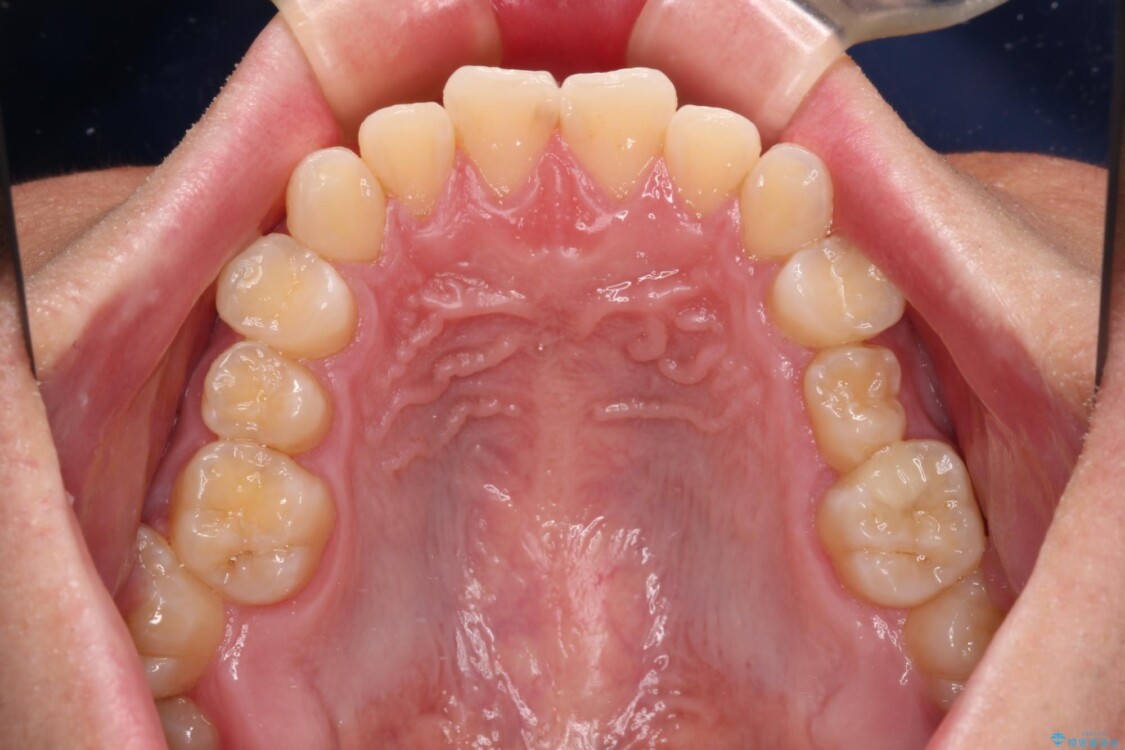

治療後

• 前歯のガタガタ・奥歯のかみ合わせ(シザーズバイト)を改善|1年半で完了したメタルブラケット矯正 治療後画像